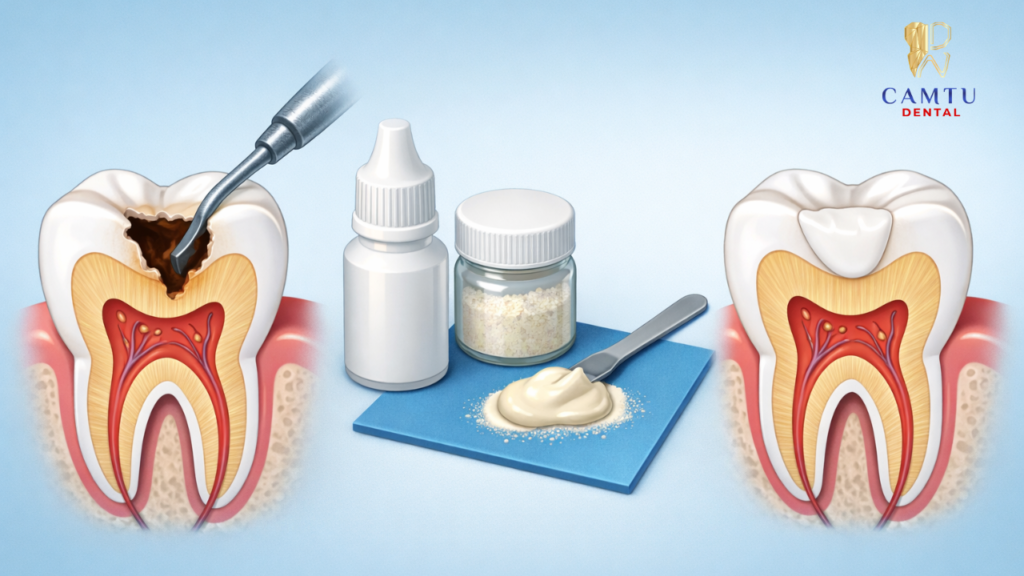

Trám răng Glass Ionomer (GIC) là kỹ thuật sử dụng vật liệu trám có thành phần chính gồm bột thủy tinh silicate và acid polyacrylic để phục hồi phần mô răng bị tổn thương. Khi trộn hai thành phần này với nhau, vật liệu sẽ tạo thành một hỗn hợp có khả năng bám dính trực tiếp lên bề mặt răng.

Sau khi loại bỏ mô răng bị sâu và làm sạch khoang trám, bác sĩ sẽ đặt vật liệu GIC vào vị trí cần phục hồi. Miếng trám giúp che phủ vùng răng tổn thương, ngăn vi khuẩn tiếp tục tấn công và hỗ trợ duy trì chức năng ăn nhai.

Sau khi xác định vị trí cần điều trị, bác sĩ sẽ tiến hành loại bỏ phần mô răng bị sâu hoặc hư hại bằng các dụng cụ nha khoa chuyên dụng. Bước này nhằm loại bỏ hoàn toàn vi khuẩn và mô răng bị tổn thương để tạo nền sạch trước khi trám.

Việc làm sạch kỹ lưỡng giúp vật liệu Glass Ionomer bám dính tốt hơn vào cấu trúc răng tự nhiên, đồng thời hạn chế nguy cơ sâu răng tái phát dưới miếng trám sau khi hoàn tất điều trị.

Bước 3: Trám vật liệu GIC

Sau khi vùng răng bị sâu đã được làm sạch và chuẩn bị, bác sĩ sẽ tiến hành trộn vật liệu Glass Ionomer theo tỷ lệ phù hợp. Vật liệu này sau đó được đặt trực tiếp vào vùng răng cần phục hồi để lấp đầy phần mô răng bị mất.

Bác sĩ sẽ tạo hình miếng trám sao cho phù hợp với cấu trúc tự nhiên của răng, đảm bảo khả năng ăn nhai và tính thẩm mỹ. Sau khi vật liệu cứng lại, miếng trám sẽ bám chắc vào răng và giúp bảo vệ vùng răng đã được điều trị.